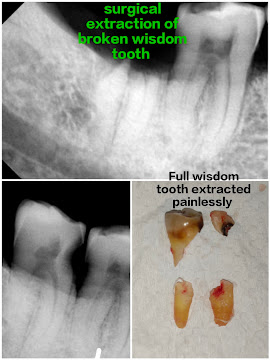

Gallery CASES DONE BY US DENTAL IMPLANT STAGE 2 SURGERYCOMPOSITE VENEERSDENTAL IMPLANT SURGERYCANINE EXPOSURE SURGERYWISDOM TOOTH SURGERYPOST AND CORE BUILD UP CALL US NOW